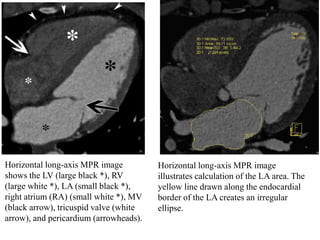

Horizontal Long-Axis View.—The horizontal long-axis view, or four-

chamber view, is a horizontal plane through the heart that essentially

bisects all four cardiac chambers.

The resultant display readily allows assessment of chamber size and

valve position. The septal, apical, and lateral LV walls can be

simultaneously assessed.

The lateral wall of the LV is normally thin at the apex (typically 1–2

mm), even in abnormally thickened hearts.

Subjective evaluation of AV valvular and ventricular function is usually

also possible in cine mode.

LA size can readily be determined. An area of less than 20 cm2 is

normal, 20–30 cm2 is mildly abnormal, 30–40 cm2 is moderately

abnormal, and greater than 40 cm2 is severely abnormal

Horizontal long-axis MPR image

shows the LV (large black *), RV

(large white *), LA (small black *),

right atrium (RA) (small white *), MV

(black arrow), tricuspid valve (white

arrow), and pericardium (arrowheads).

illustrates calculation of the LA area. The

yellow line drawn along the endocardial

border of the LA creates an irregular

ellipse.